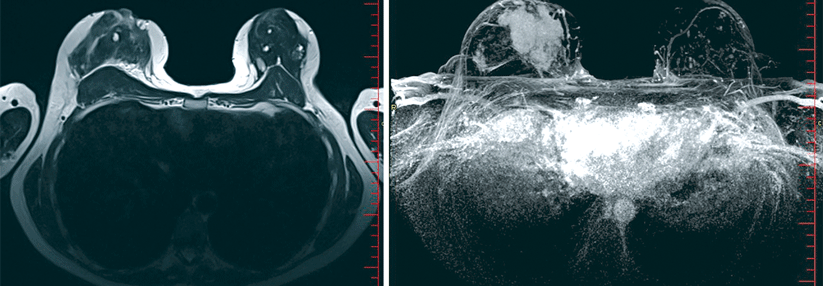

Prof. Hackelöer beschreibt, dass die Mammographie – im Gegensatz zum Ultraschall – keinen so klaren Kontrast zwischen dem Tumor und dem übrigen Drüsen- und Bindegewebe aufweist. Karzinome könnten deshalb durch das übrige restliche Drüsen- und Bindegewebe maskiert oder verborgen werden. Besonders häufig sei das bei Frauen mit dichtem Gewebe der Fall – etwa bei der Hälfte der Frauen im Alter ab 50 Jahren.